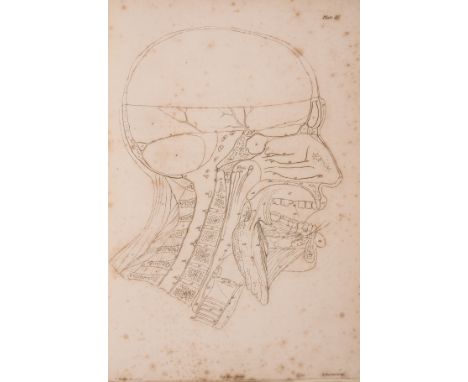

Anatomy.- Tortebat (François) Abregé d'Anatomie, accomodé aux Arts de Peinture et de Sculpture, second edition, engraved pictorial title, 10 engraved full-page illustrations after Vesalius, some spotting and light marginal staining, old marbled wrappers, a little rubbed and stained, spine repaired, preserved in modern cloth folder and slip-case, Paris, J.B.Crepy, 1760; and an Atlas of 13 engraved plates illustrating Scarpa's anatomy (4 with partial hand-colouring), folio (2)⁂ The second most important work on anatomy for the use of artists, first published in 1667 and preceded only by van der Gracht's Anatomie... of 1634. The plates are taken from Vesalius, re-engraved and reversed, and feature male figures as skeletons or displaying their muscles, tendons, etc.

Anatomy.- Watt (John James) Anatomico-Chirurgical Views of the Nose, Mouth, Larynx, & Fauces..., first edition, 4 fine hand-coloured stipple-engraved plates by J.Hopwood after T.Baxter, each with accompanying engraved outline plate, text and outline plates spotted but hand-coloured plates generally clean, some marginal soiling to title and text, old bookplate of John W.Walker, contemporary half calf, rubbed, rebacked, folio, 1809.⁂ The first coloured illustrations of the anatomy of the nose and throat to be published.